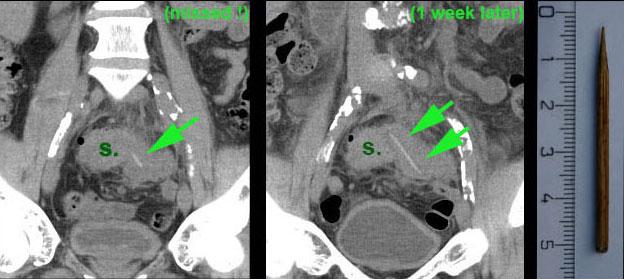

Bệnh nhân nam 57 tuổi (tiền sử cắt ruột thừa) với nghi ngờ viêm túi thừa.

CT cho thấy dày thành đại tràng sigma (s.) và một khối không rõ ràng ở phía trái.

Tại thời điểm này, đường tăng âm nhỏ (mũi tên) đã bị bỏ sót.

Chẩn đoán CT là viêm túi thừa đại tràng sigma hoặc ác tính đại tràng sigma.

Nội soi đại tràng không tiếp cận được vùng này.

Trên CT lặp lại một tuần sau, chúng tôi may mắn khi dị vật sắc nhọn thẳng và hơi tăng âm (mũi tên) lần này hiện ra toàn bộ chiều dài trên CT mặt phẳng coronal.

Trong phẫu thuật, một phần đại tràng sigma được cắt bỏ cùng với một khối viêm lớn, chứa que tăm cocktail bằng gỗ là nguyên nhân gây bệnh.

Một hậu môn nhân tạo tạm thời đã được tạo ra.

Bệnh nhân tỏ ra không tin và kiên quyết phủ nhận việc đã nuốt phải que đó.